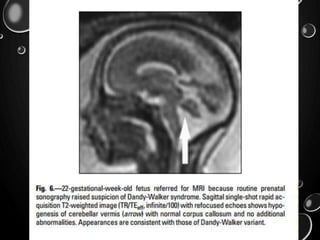

• DANDY-WALKER SYNDROME, - ADDITIONAL

ABNORMALITIESTHAT INDICATE A WORSE PROGNOSIS,

INCLUDINGAGENESIS OF THE CORPUS CALLOSUM,

POLYMICROGYRIA, NEURONAL HETEROTOPIA, AND

OCCIPITAL ENCEPHALOCELE.